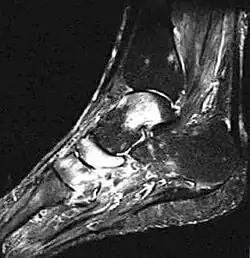

- Fuß, MRT, T2-Gewichtung

-

Knochenmarködem (hell) in Sprungbein, Kahnbein und Keilbein -